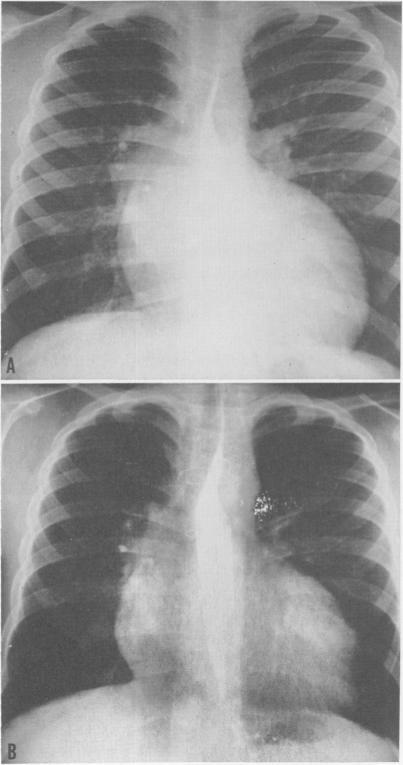

Surgical treatment of idiopathic hypertrophic subaortic stenosis: technic and hemodynamic results of subaortic ventriculomyotomy.

Ann Surg. 1961 Aug;154(2):181-9. doi: 10.1097/00000658-196108000-00003.